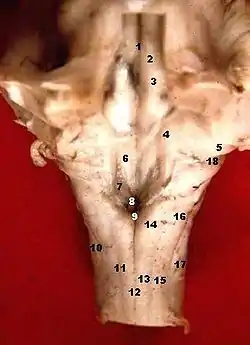

Human caudal brainstem posterior view (Colliculus facialis is #3) | |

The facial colliculus is an elevated area located in the pontine tegmentum (dorsal pons), within the floor of the fourth ventricle (i.e. the rhomboid fossa). It is formed by fibres from the facial motor nucleus looping over the abducens nucleus. The facial colliculus is an essential landmark of the rhomboid fossa.[1]

The facial colliculus occurs within the rhomboid fossa (i.e. the floor of the fourth ventricle) where it is placed lateral to its (midline) median sulcus.[1]